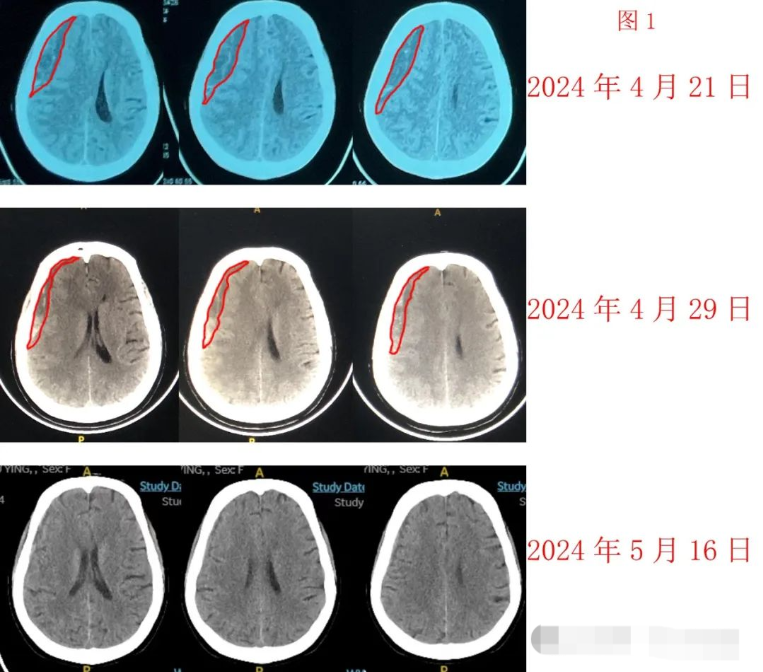

今年以來,我線上線下、門診住院新治療的慢性硬膜下血腫患者已經超過50位了,但因為無效而轉為手術的不到5位,療效非常滿意。而隨著求診于我的慢性硬膜下血腫患者越來越多,一些特殊患者也就涌現(xiàn)出來,讓我加深了對影響慢性硬膜下血腫藥物治療療效因素的認識。由于還是不斷有醫(yī)生同行告訴我說他們的治療對患者有時無效,因此,我愿意把我的經驗分享給大家。病例1.男性,73歲患者因輕微外傷導致硬膜下血腫,堅決拒絕手術。因血腫較大,已經影響他走路,遂于2024年01月16日入院接受他汀加激素加頭頸淋巴引流按摩治療。由于他還有嚴重的糖尿病,我迅速降低了激素劑量。治療7天后,他的血腫體積看上去似乎無變化,但癥狀緩解;我就讓他再住院1周,延續(xù)他汀加激素治療,結果第2次復查他的硬膜下血腫的枕葉部分體積增多、而額葉部分體積減少,這種變化很特殊,也讓我猶豫半天,最后根據(jù)患者意愿放他出院。2024年02月08日他突然左側肢體活動變差,急診復查影像學并無特殊異常發(fā)現(xiàn),因此未做進一步處理。待患者完成了4周的他汀加激素治療后,開始轉變?yōu)橹环冒⑼蟹ニ♀}。但多次復查,他的血腫體積只是略微縮小,癥狀略微緩解,狀態(tài)卻始終沒有恢復到生病之前。因為行動仍然不便,每次都是他家人來門診隨訪和開藥,也讓我有點焦慮地一直牽掛著他的病情,并多次溝通希望他接受手術治療,但是老人家非常堅定,只要病情沒有加重就不手術。我后來了解到,他的頭頸淋巴按摩始終不規(guī)范,每天連1次按摩也不夠,遂說服他家人,一定堅持規(guī)范按摩1個月,我們再復查。輾轉到了2024年3月底,再次門診時,他家人告訴我老爺子現(xiàn)在扶著東西可以自己走幾步了。我迫切希望看到患者的復查影像,但我也不希望患者接受過于頻繁的檢查。因此,直到2024年4月13日才讓他家人掛互聯(lián)網(wǎng)診療號安排他做復查,也是我第一次看到老人家的血腫明顯減少(圖1,紅線范圍為血腫)。圖1我十分高興,立即把喜悅分享給了患者家屬。我問這個患者的家人,她父親從2024年1月開始接受我治療,到4月13日才看到了肯定的療效,是否會后悔沒有及早做手術?這個時間代價是否值得?他家人回答:時間不是問題,沒有做手術還有療效,是她最希望看到的。我由衷感謝這位患者家人對我的信賴和堅持。我還從這病例中得到經驗:1.慢性硬膜下血腫的藥物治療是需要堅持的;2.頭頸淋巴引流按摩可能在發(fā)揮重要的輔助療效。病例2,男性,77歲患者因為外傷導致頭痛頭暈,到醫(yī)院檢查后確診為雙側硬膜下血腫,其中右側血腫巨大。老人家拒絕手術。接診他的是我?guī)Ы踢^的學生,他很關注我的治療,也模仿我使用他汀加激素療法治療這例患者。結果,患者從2024年2月24日接受他的治療,3月9日復查發(fā)現(xiàn)左側血腫明顯吸收,右側血腫則變化不明顯。到4月14日,患者突然雙下肢乏力,急查頭CT見左側血腫消失殆盡,右側則明顯比3月9日增多,像是左側血腫跑到了右側。奇怪的是,盡管血腫如此巨大,甚至超過我以前報告過的那位業(yè)余作家的血腫,但這位患者的CT影像中線移位卻不顯著,也因此,老人家始終神志清醒,除了雙腿乏力,照常吃喝不愁。我這位學生求助于我的團隊。我分析認為,人的雙側硬膜下腔與老鼠不同,老鼠雙側是相通的,人類的硬膜下腔雙側是隔離獨立的,故推測他的左側吸收和右側增大沒有直接關系,并不是左側的跑到右側去了,肯定另有原因。追問病史得知,患者在3月9日復查得知血腫吸收良好后,開始增大了活動量,并在4月14日之前多次感到疲憊不堪,這可能導致右側血腫增大。但我堅持認為,患者的左側血腫對藥物治療敏感,右側血腫的藥物治療應該也會有效。我決定收他入院,再次施予他汀加激素治療,另外還親自指導患者自己做頭頸淋巴引流按摩。他于4月18日入院,接受我的治療方案。4月24日治療滿7天,CT復查顯示他的右側血腫也開始顯著減少(圖2,紅線范圍為血腫),老人下肢活動也已經基本如常,我果斷放他出院療養(yǎng)。老人家興高采烈地回家了。圖2這例患者給我的啟示是,慢性硬膜下血腫的藥物治療中必須交待患者遵守一些注意事項。我先后總結并提出了12個注意事項,包括短時間內禁止口服活血化瘀藥物、禁止提重物、禁止在頭頸交界部拔罐子等等……雖然這些注意事項與慢性硬膜下血腫藥物療效之間的因果關系沒有得到嚴格臨床論證,但是,每個注意事項的總結都是有相關病例的治療經驗作為旁證的。我覺得這些注意事項要做到很容易,代價很低,也因此就把它作為慢性硬膜下血腫治療方案的一部分內容加以推廣。很多外地醫(yī)生向我索要治療方案,我通常都是毫無保留地告訴他們我的經驗,也告訴他們注意事項,但是,總體來說,他們治療失敗的患者比我多。我推想其他醫(yī)生治療失敗的原因可能有多種,但我?guī)缀蹩梢钥隙?,有些失敗就是源于患者沒有遵守我總結的注意事項。總之,我們的藥物治療慢性硬膜下血腫方案的有效率已經超過90%,多數(shù)患者僅需付出時間的代價,無需承擔手術風險,患者、家庭和社會付出的代價極低。最多時,我的病房里同時住著4位慕名求診來的、來自全國各地的慢性硬膜下血腫患者,說明我的治療得到患者廣泛歡迎。雖然業(yè)界公認慢性硬膜下血腫的一線治療是手術治療(包括鉆孔引流、錐孔引流、開顱手術、內鏡手術和硬腦膜中動脈栓塞術等),但即使是鉆孔引流,也具有風險。我剛剛會診的一例外地慢性硬膜下血腫患者,經歷了鉆孔手術、開顱手術,卻無法消滅血腫,反而導致患者昏迷超過28天,至今還在植物狀態(tài),十分令人痛心。我知道我們的藥物治療要獲得業(yè)界同行普遍認可,還需假以時日。我有耐心守候這個時間的到來,我也會繼續(xù)努力向社會推廣這項好方案。專家介紹江榮才教授二級教授,主任醫(yī)師,博導,海河醫(yī)學學者天津醫(yī)科大學總醫(yī)院神經外科中心常務副主任,科副主任,NICU主任天津市131第一層次人才,天津市醫(yī)學會神經重癥分會首任主任委員,天津市醫(yī)學會神經外科副主任委員中華醫(yī)學會神經外科學分會委員、腦外傷學組副組長中國醫(yī)師協(xié)會神經外科醫(yī)師協(xié)會神經重癥專委會副主任委員國家創(chuàng)傷醫(yī)學中心顱腦創(chuàng)傷專業(yè)委員會副主任委員中國老年保健協(xié)會神經外科學創(chuàng)新與轉化分會首任會長擅長復雜重型腦外傷、腦出血及慢性硬膜下血腫的診療。是他汀治療硬膜下血腫的主要發(fā)明者,治療慢性硬膜下血腫患者超1000名,總治愈率約90%